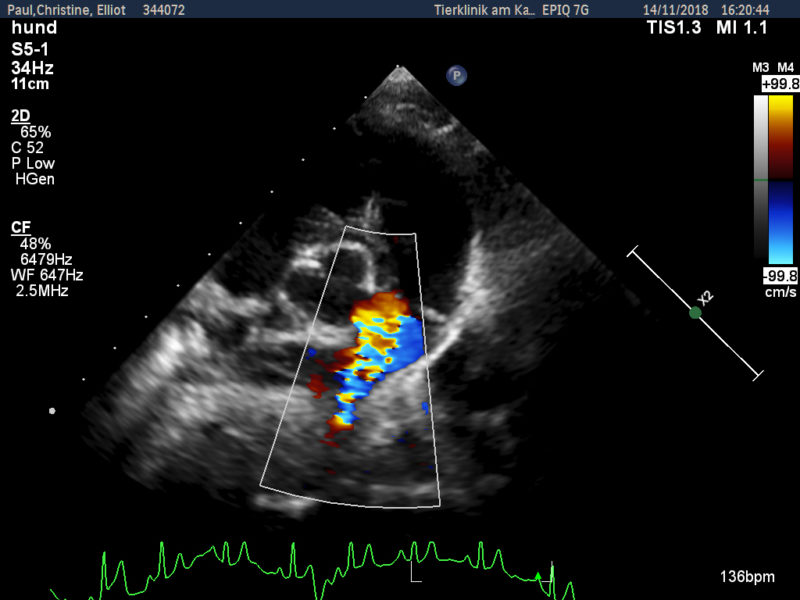

Zunächst wurde von den Kollegen - aufgrund des zeitlichen Zusammenhangs - eine Impfreaktion vermutet, woraufhin Elliot starke Schmerzmittel bekam. Allerdings besserte sich seine Lahmheit weder durch Schmerzmittel noch durch Kortison wesentlich. Da man äußerlich nichts feststellen konnte, wurde eine erste Röntgenuntersuchung des Rumpfes durchgeführt, bei der aber die Ursache leider nicht gefunden wurde. Als auch nach dieser weder Fieber noch Lahmheit verschwanden, wurde der Hund zur Spezialdiagnostik überwiesen. Es sollte nun bei uns in der Klinik erneut geröntgt und eventuell eine Computertomographie durchgeführt werden. Bei der Eingangsuntersuchung vor der notwendigen Narkose wurde ein kontinuierliches Herzgeräusch festgestellt. Dieses konnte nur unter dem linken Schulterblatt in Höhe des 2.-3. Zwischenrippenraumes auskultiert werden. An dieser Stelle war es aber sehr laut (Grad 5 von 6) und gut hörbar. Der untersuchende Kardiologe stellte einen klinisch relevanten PDA (Ductus arteriosus botalli persistens) fest, der sich schon in einem behandlungswürdigen Stadium befand. Daher war an eine Narkose zur Abklärung der Lahmheit an diesem Tage nicht zu denken.

Erfreulicherweise verschwindet die Erkrankung mit Ende des Knochenwachstums. Für Elliot zunächst aber das kleinere Problem. Ein PDA, wie er im Herzen von Elliot festgestellt wurde, verläuft für fast 2/3 der Welpen im ersten Lebensjahr tödlich. Daher muss dieser verschlossen werden. Bei dem PDA handelt es sich um ein Blutgefäß, welches sich nach der Geburt nicht ordnungsgemäß verschlossen hat. Deshalb fließt Blut auch nach der Geburt an der Lunge vorbei zurück in das linke Herz, welches sich daraufhin stark vergrößert.

Durch die besondere Krankengeschichte von Elliot mit den seit Wochen erhöhten Entzündungswerten, haben wir uns entschlossen, kein Implantat mittels Katheter einzulegen, um keine Abstoßungsreaktionen des Implantates in einem Blutgefäß zu riskieren (Thrombosegefahr). Daher wählten wir den offen chirurgischen Weg, um das PDA-Gefäß von außen zu verschließen. Da seine Entzündungswerte (C-reaktives Protein) sehr hoch waren, wurden zunächst nichtsteroidale Antiphlogistika verabreicht und regelmäßig kontrolliert. Nach Absinken der Entzündungswerte wurde der Eingriff durchgeführt. Das Gefäß wurde ohne nennenswerte Komplikationen verschlossen und Elliot am Folgetag entlassen.